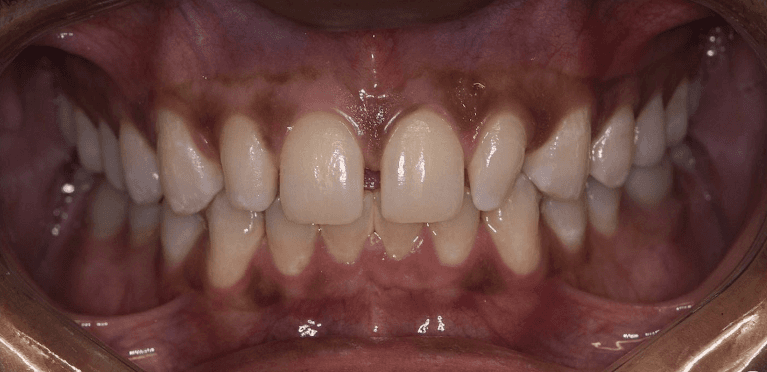

Before and after with Invisalign orthodontic treatment. Pictures taken with different phones at different setting. Used total of 27 aligners/trays. Treatment time 13.5 months